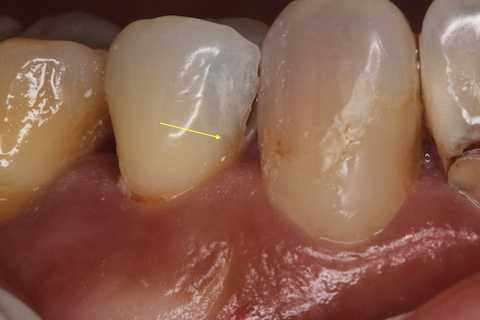

では術前、術中、術後の画像を時系列でどうぞ

術後の画像ではクラックが良く見えると思う。